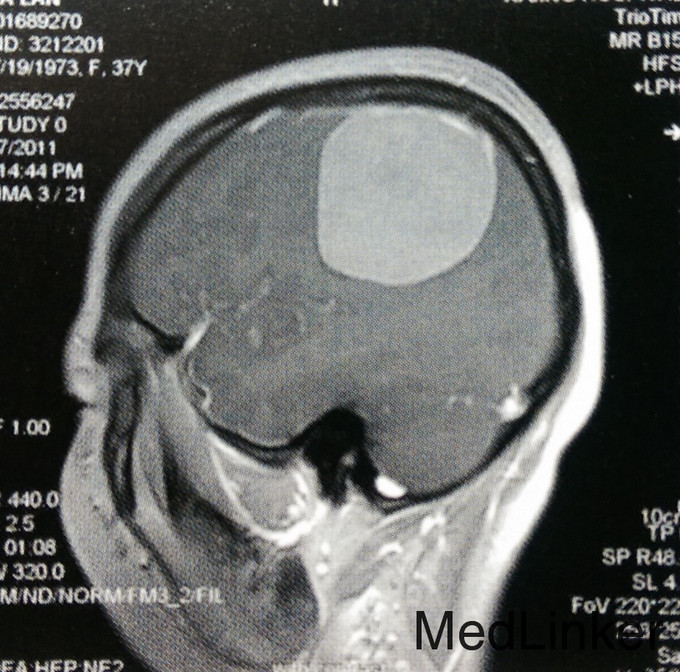

患者,女,37岁。主因左上肢麻木2年入院。 患者2年前无诱因出现左侧肢体麻木,无乏力、活动受限,未就诊。此后上述症状进行性加重,遂在当地医院以颈椎病对症治疗,未好转。行头颅MRI检查:右侧颞顶枕部见类圆形占位,大小约5.8cmх5.2cmх5.4cm,T1WI呈稍低信号,T2WI呈稍高信号,边缘尚清楚,压迫右侧脑室后角。Gd-DTPA增强后,明显强化,合并宽基底与脑膜相接,可见鼠尾征。门诊以“右顶叶巨大肿瘤”收入我科。无相关既往史、个人史及家族史。

诊断:颞顶枕巨大脑膜瘤一例 患者在全麻下行“开颅右侧颞顶枕巨大肿瘤切除术”。